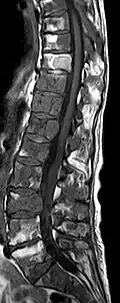

- Comparaison scanner/IRM pour des métastases ostéolytique d'un cancer du sein dans la colonne vertébrale

Scanner sagittal reconstruit, représentation dans la fenêtre osseuse. Comme la patiente avait des métastases dans toutes les régions du corps, elle ne pouvait pas lever les bras pour l'examen, ce pourquoi les mains sont présentées.

Scanner sagittale, parties molles. Outre les métastases dans la colonne vertébrale, qui envahissent en partie le canal médullaire vers l'arrière, métastases aussi dans le sternum. Plus des métastases dans le foie.

IRM natif avec pondération T1.

IRM sagittal natif avec pondération T1. On voit clairement l’extension jusqu'aux lames vertébrales.